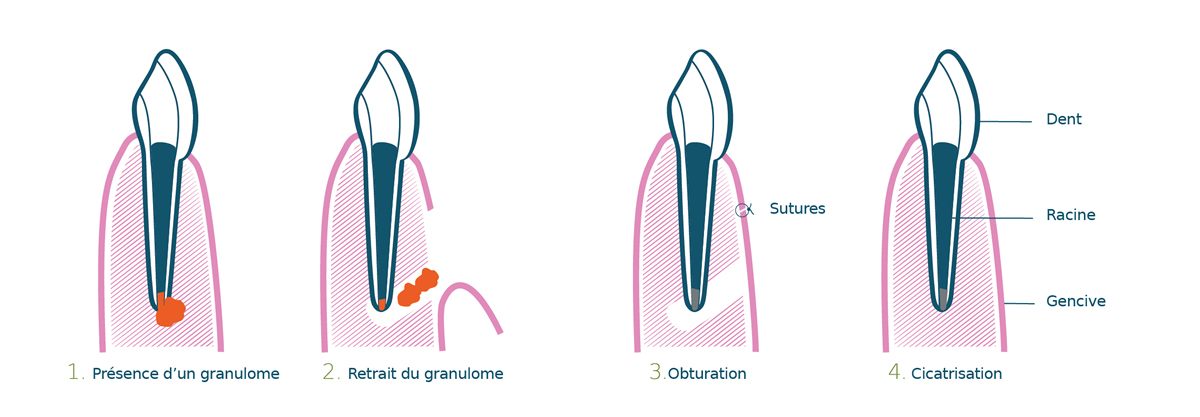

LES ETAPES DE LA RESECTION APICALE

Elle consiste à éliminer l’infection par un abord chirurgical, puis à désinfecter à nouveau la dent mais cette fois ci en passant par la racine (traitement rétrograde) et non par la couronne dentaire (traitement orthograde).

La microchirurgie endodontique est indiquée lorsque le retraitement endodontique est impossible.

C’est le cas quand une couronne ne peut être enlevée ou quand un retraitement n’a pas permis de résoudre l’infection.